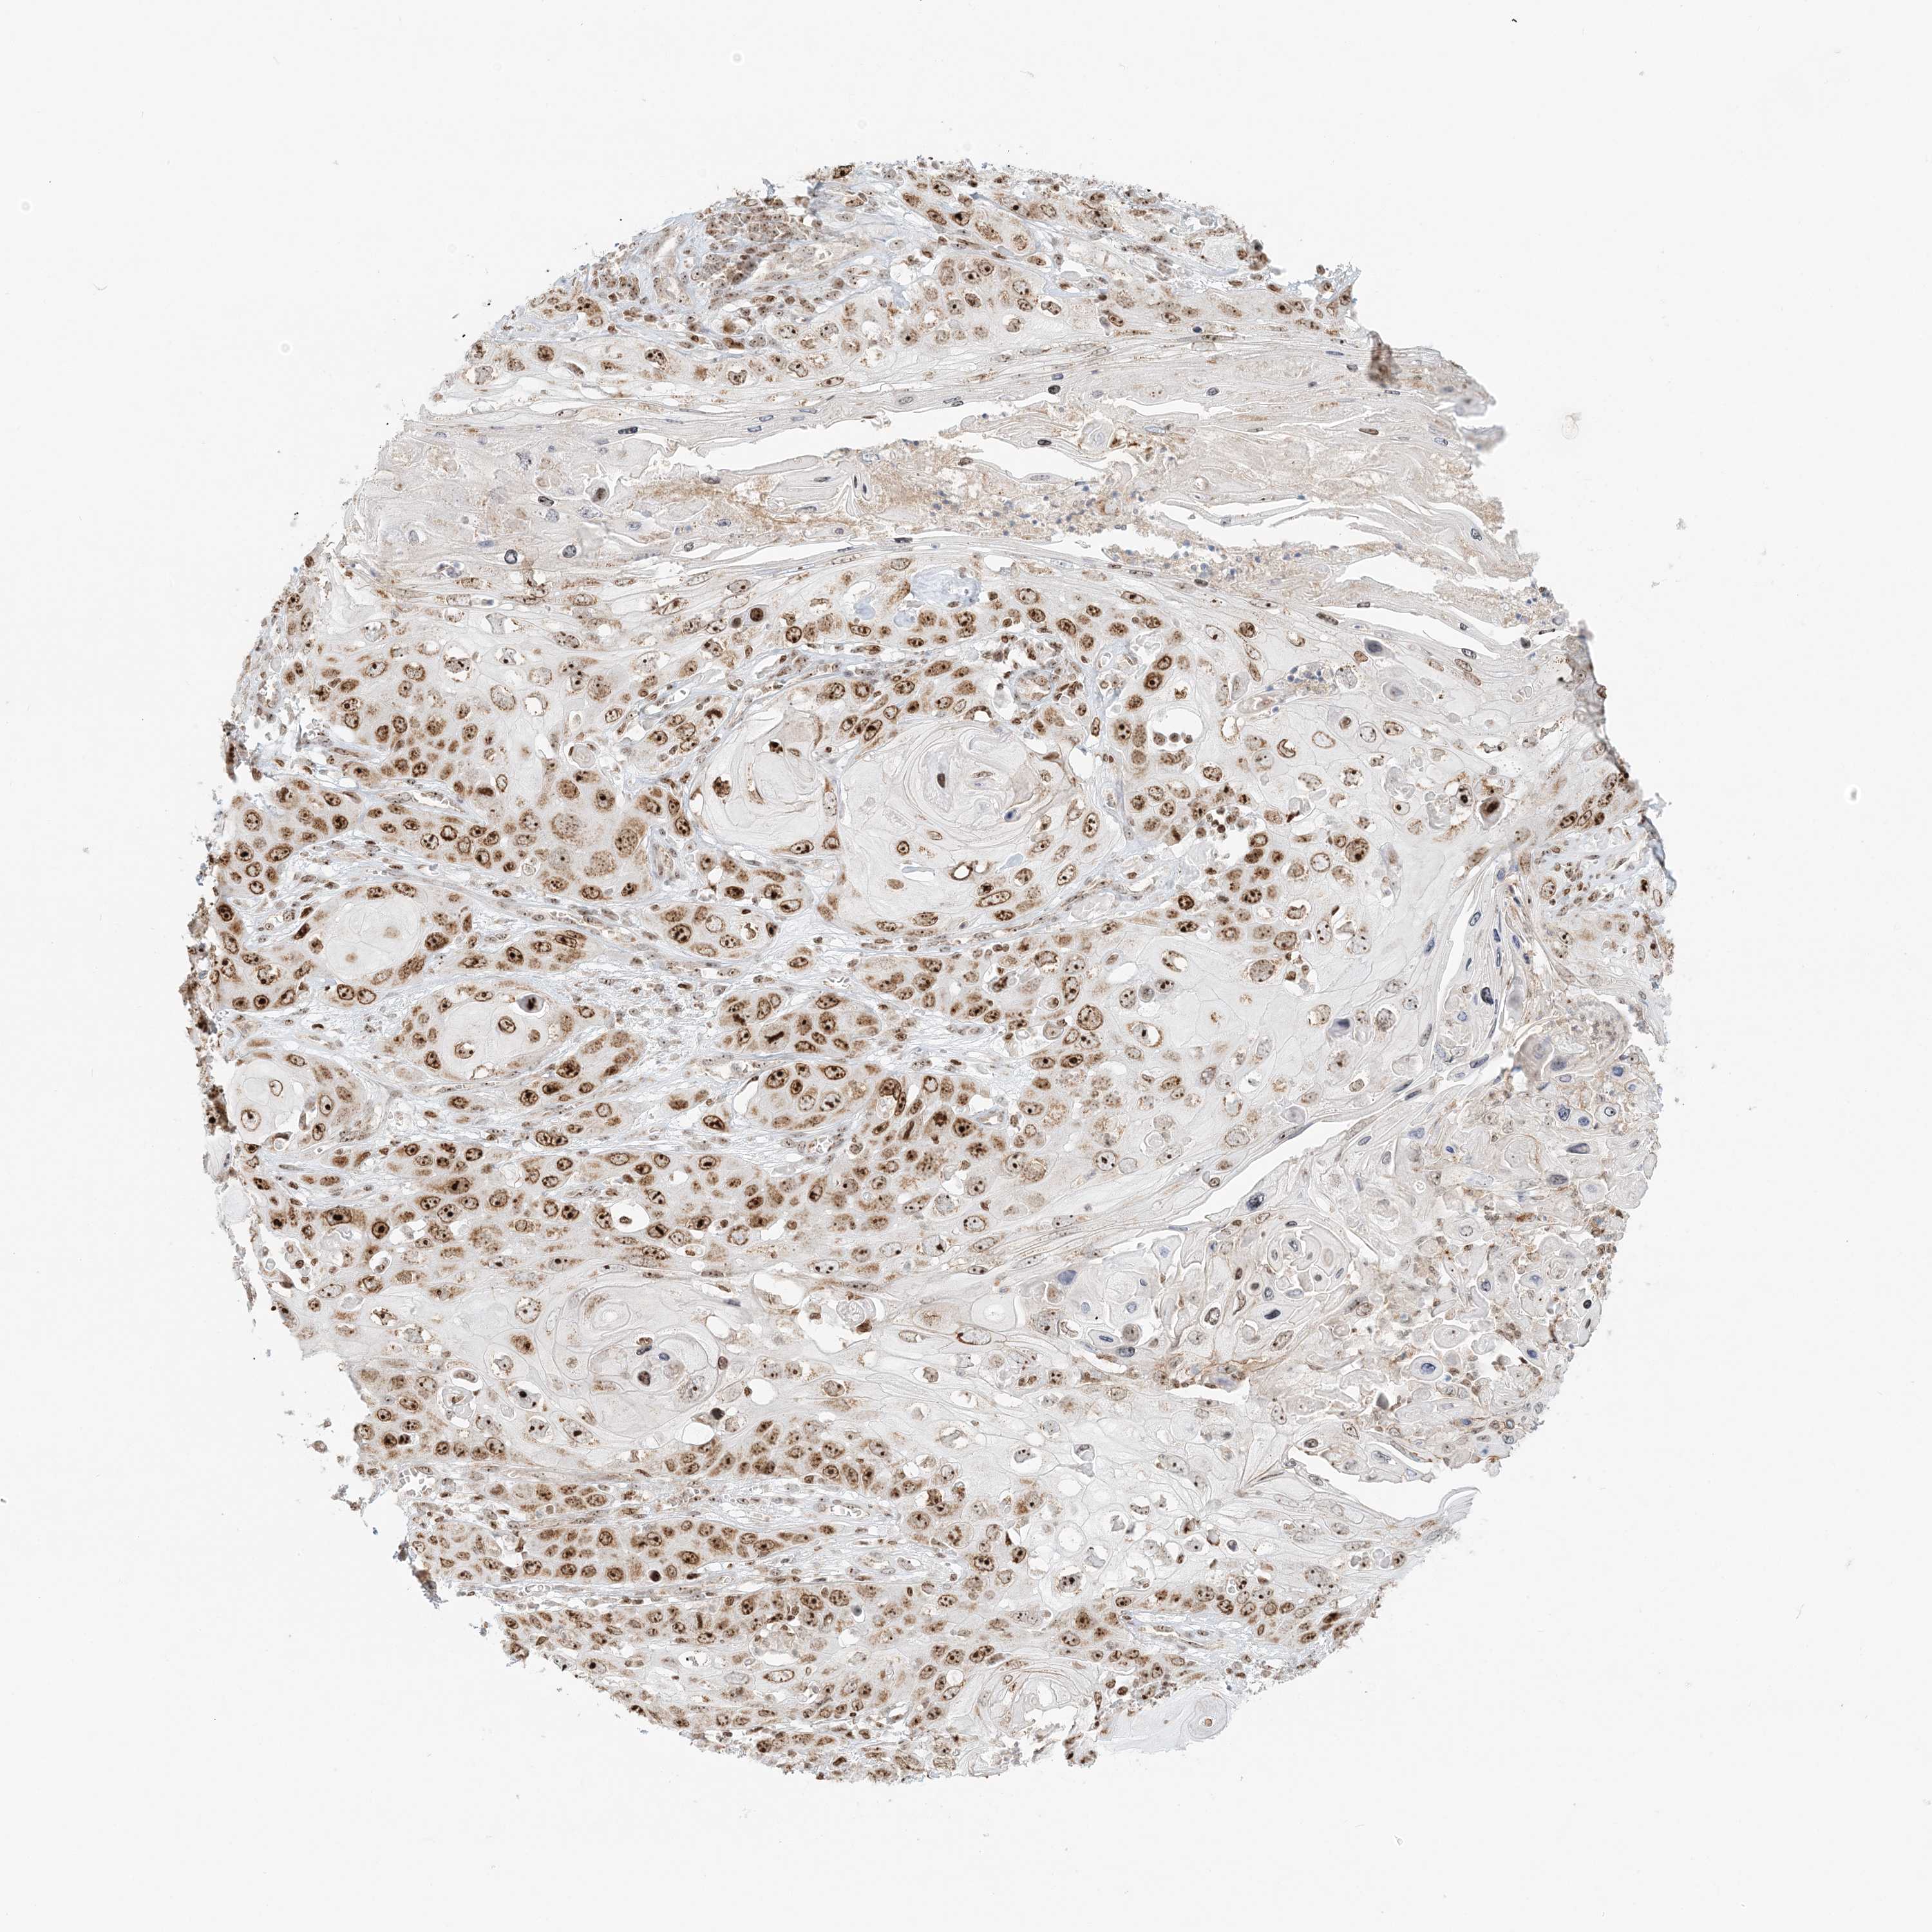

Basal cell and squamous cell cancer

SKIN CANCER - Protein expressioni

A mouse-over function shows sample information and annotation data. Click on an image to view it in a full screen mode. Samples can be filtered based on level of antibody staining by selecting one or several of the following categories: high, medium, low and not detected. The assay and annotation is described here.

Antibody stainingi

Antibody staining in the annotated cell types in the current human tissue is reported as not detected, low, medium, or high, based on conventional immunohistochemistry profiling in selected tissues. This score is based on the combination of the staining intensity and fraction of stained cells.

Each image is clickable and will lead to virtual microscopy that enables deeper exploration of all samples and also displays staining intensity scores, fraction scores and subcellular localization as well as patient and tissue information for each sample.

Antibody HPA037444

Staining

High

Intensity

Strong

Quantity

>75%

Location

Nuclear

Basal cell carcinoma

Squamous cell carcinoma, NOS

Squamous cell carcinoma, metastatic, NOS